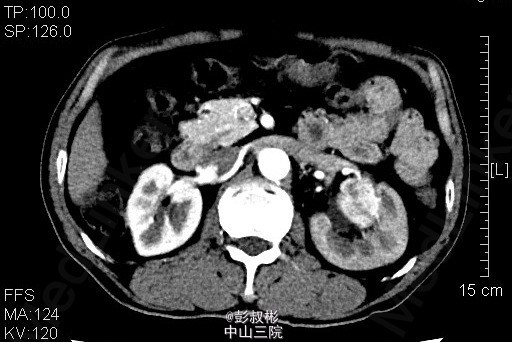

男性,51岁,发现左肾肿物2年余。反复左腰部隐痛2月余,无肉眼血尿。泌尿系B超:左肾中极见一个类圆形低回声光团,大小:30×26mm,边界不清,内部回声欠均匀。左肾实性占位病变。腹部CT:左肾占位病变,考虑为肾癌可能性大。